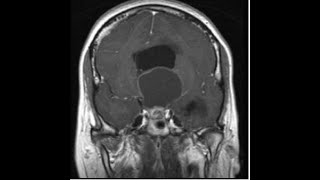

o núcleo dorsomedial com os lucros do grupo anterior e também na ativação do córtex como um todo em uma ação menos específicas e por exemplo com núcleo centromediano então veja a diversidade de funções neurais participação notável a e aqui na ressonância no exame de imagem e se a gente tomar um corte exatamente mediano vai ser difícil de ver o talão o talão estrutura para mediana então se eu cortar no sagital exatamente no terceiro ventrículo aqui não vou ver o talo se eu cortar um pouquinho para paramediano como essa outra a foto está mostrando já começa

a ver essa massa tá branca e eu começo a compreender melhor aqueles limites olha só aqui na parte anterior e inferiormente o hipotálamo e mais posteriormente o mesencéfalo e aqui um corte axial em t2 eu já vejo nitidamente o tálamo de cada lado tendo no centro o terceiro ventrículo vejo aqui a cápsula interna que o limita lateralmente e os separa dos núcleos da base como os lobos paris o time cabeça do núcleo caudado olá neste corte coronal continuo vendo as massas italianas de um lado e de outro com o terceiro ventrículo no meio porém eu

vejo essa região inferior bilateralmente e aí lateral e porta amo que são as regiões do subtálamo é composta pelo lucro subir tá mesmo aqui pela zona incerta esse assunto de uma outra discussão o luiz eram os principais aspectos que nós gostaríamos de chamar a atenção sobre a neuroanatomia funcional básica do termo espero que tem aproveitar ficamos à disposição nos diversos canais de comunicação para discutir para tirar dores e até uma próxima oportunidade e e aí